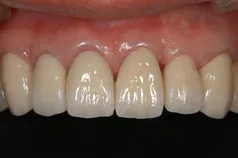

[症例1]

重度の歯周病で奥歯がすでになくなっており、そのため前歯もグラグラの状態でした。

右上の前歯(向かって左上)は自然に抜け落ちたそうです。

下の前歯の裏側には多量の歯石がたまっています。

【処置内容】

歯周初期治療、全体に歯周外科処置を実施、その後セラミックブリッジ、セラミッククラウン、

右上6・5番、左上3・4・5・6番、左下6番、右下4・6番にインプラントを実施。

• 治療期間:約2年

• 治療費:400万円

• 治療回数:30回